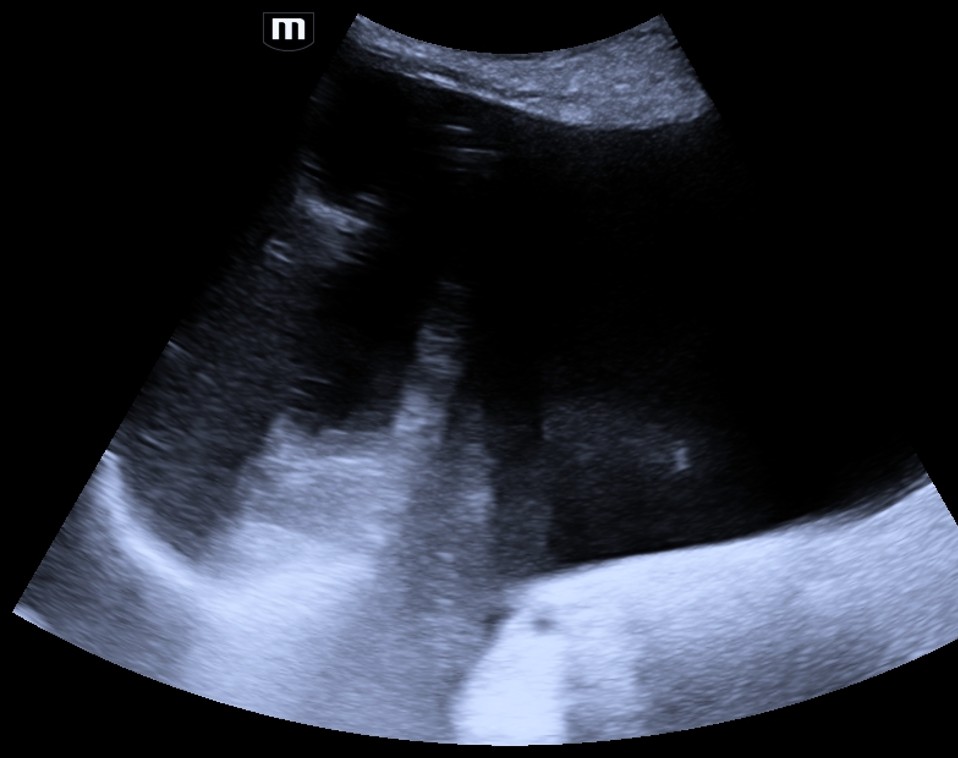

O-RADS US 0: Avaliação incompleta

O-RADS US 1: Ovário normal

O-RADS US 2: Quase certamente benigno (<1%)

O-RADS US 3: Baixo risco de malignidade (<10%)

O-RADS US 4: Risco intermediário (10-<50%)

O-RADS US 5: Alto risco (≥50%)